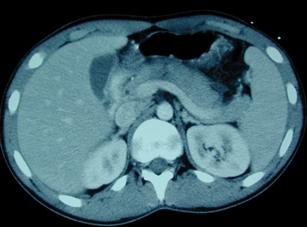

Traumatism abdominal inchis

Leziune de pancreas ( ambele foto)

Traumatism abdominal

inchis

Leziune pancreatica